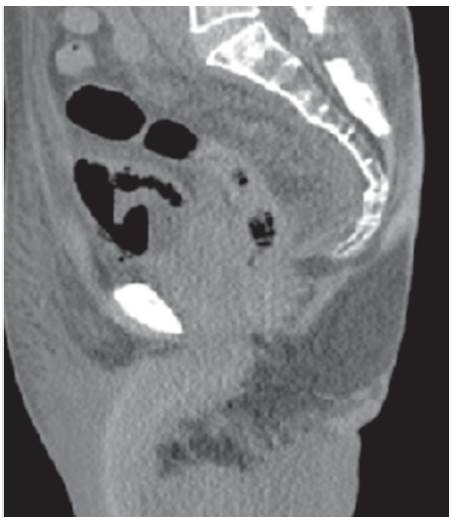

Se recibe reporte de patología, el cual evidencia tumor neuroendocrino tipo células de Merckel; entonces se valora por Oncología, donde indican inicio de quimioterapia ambulatoria, una vez se dé el egreso hospitalario. Una semana después el paciente presenta hematuria franca y oliguria; en estudios de laboratorios evidencian uroanálisis con hematuria, proteinuria en rango nefrótico y sedimento activo, con función renal dentro de parámetros de normalidad. Dados los nuevos hallazgos clínicos y el antecedente de diabetes, se decide solicitar estudios adicionales, descartando por oftalmología retinopatía diabética; adicionalmente el equipo de Nefrología descarta síndrome nefrótico, al evidenciar orina de 0,3 g en 24 horas, hipoalbuminemia y perfil lipídico normal; así mismo la morfología globular se encontraba en el 60% de hematíes eumorfos, descartando glomerulopatías. Investigando el origen de la hematuria, se complementa con estudios anatómicos; en efecto, se inicia con ecografía de vías urinarias que reportan buena diferenciación cortico-medular con riñones conservados de tamaño; posteriormente se solicita UROTAC para observar el tracto urinario bajo, evidenciándose engrosamiento de la pared vesical, gas perivesical como se observa en las imágenes 1, 2 y 3, y con conglomerados ganglionares retroperitoneales, hallazgos compatibles con cistitis enfisematosa.

Dado el hallazgo anterior se solicita urocultivo y baciloscopia en orina para determinar la etiología, y adicionalmente se pide valoración por urología, descartando indicación de manejo quirúrgico. Las baciloscopias seriadas de orina son negativas y en el urocultivo se aisla E. coli patrón BLEE; se indicó continuar manejo antibiótico con ertapenem por 14 días y seguir con sonda vesical; posteriormente cesa hematuria macroscópica y aumento el gasto urinario. En relación con conglomerados ganglionares descritos, se planteó posible compromiso tumoral para posterior seguimiento de forma ambulatoria con servicio de oncología. Ver cuadro paraclínicos.

Para el diagnóstico de la CE y para descartar diagnósticos diferenciales como fístula vésicocólica, abscesos intraabdominales, neoplasias adyacentes y pielonefritis enfisematosa, se hace necesario el uso de métodos imagenológicos como la radiografía abdominal convencional simple, la ecografía abdominal y la tomografía computarizada, donde pueda ser evidenciado el gas en la vejiga, el engrosamiento de las paredes vesicales9.

El caso aquí reportado se correlaciona con lo encontrado en la literatura desde el punto de vista del aislamiento microbiológico que corresponde a una Escherichia coli, aunque el nuestro es una E. Coli con patrón de resistencia a betalactamasas de espectro extendido (BLEE), probablemente por las complicaciones anotadas, como la hospitalización previa para el manejo posoperatorio del colgajo de piel y el uso de antibióticos en dicha hospitalización. También, se correlaciona con la literatura en la presentación del cuadro clínico, el antecedente de diabetes como el factor de riesgo más asociado, y en el abordaje diagnóstico, en el cual se pudo documentar el aire perivesical por medio del UROTAC, que es el examen con mayor sensibilidad y especificidad para el diagnóstico de esta patología.